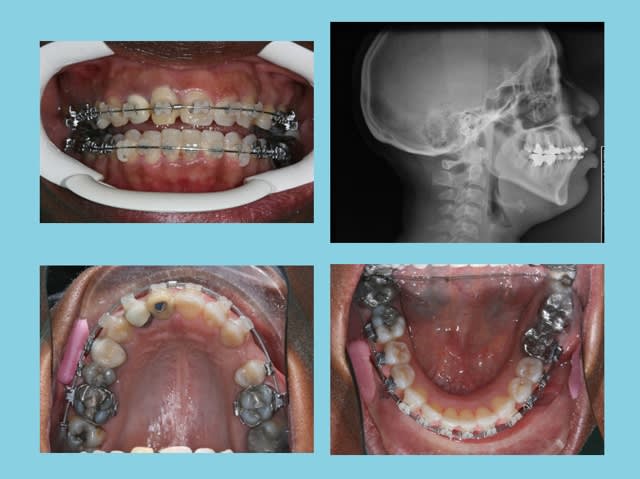

PHOTOS

Debut 1 zymdmr - Eugenol

Fin 1 xfreq4 - Eugenol

Mesures 1 ev0m2u - Eugenol